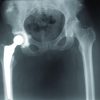

A 52-year-old female presented to us with pain in the right hip and inability to bear weight since 1 week ago following an episode of trivial fall, the patient also gave a history of dull aching pain in the left hip since the past 2 months. Bilateral hip examination revealed tenderness in both the proximal thigh, with flexion and external rotation deformity of the right lower limb. On subsequent X-rays, it was found that the patient had a right sided intertrochanteric fracture and a left-sided undisplaced unicortical fracture at the level of the lesser trochanter. The patient was a diagnosed case of HIV on ART comprising dolutegravir, lamivudine, and tenofovir since past 10 years. The patient was operated with closed reduction and internal fixation with a proximal femoral nail bilaterally. Post-operative period was uneventful and the patient was wheelchair mobilized initially and discharged after 5 days. The patient gradually progressed later to walking with the aid of a walker. A subsequent follow-up at 3 months revealed a uniting fracture bilaterally.